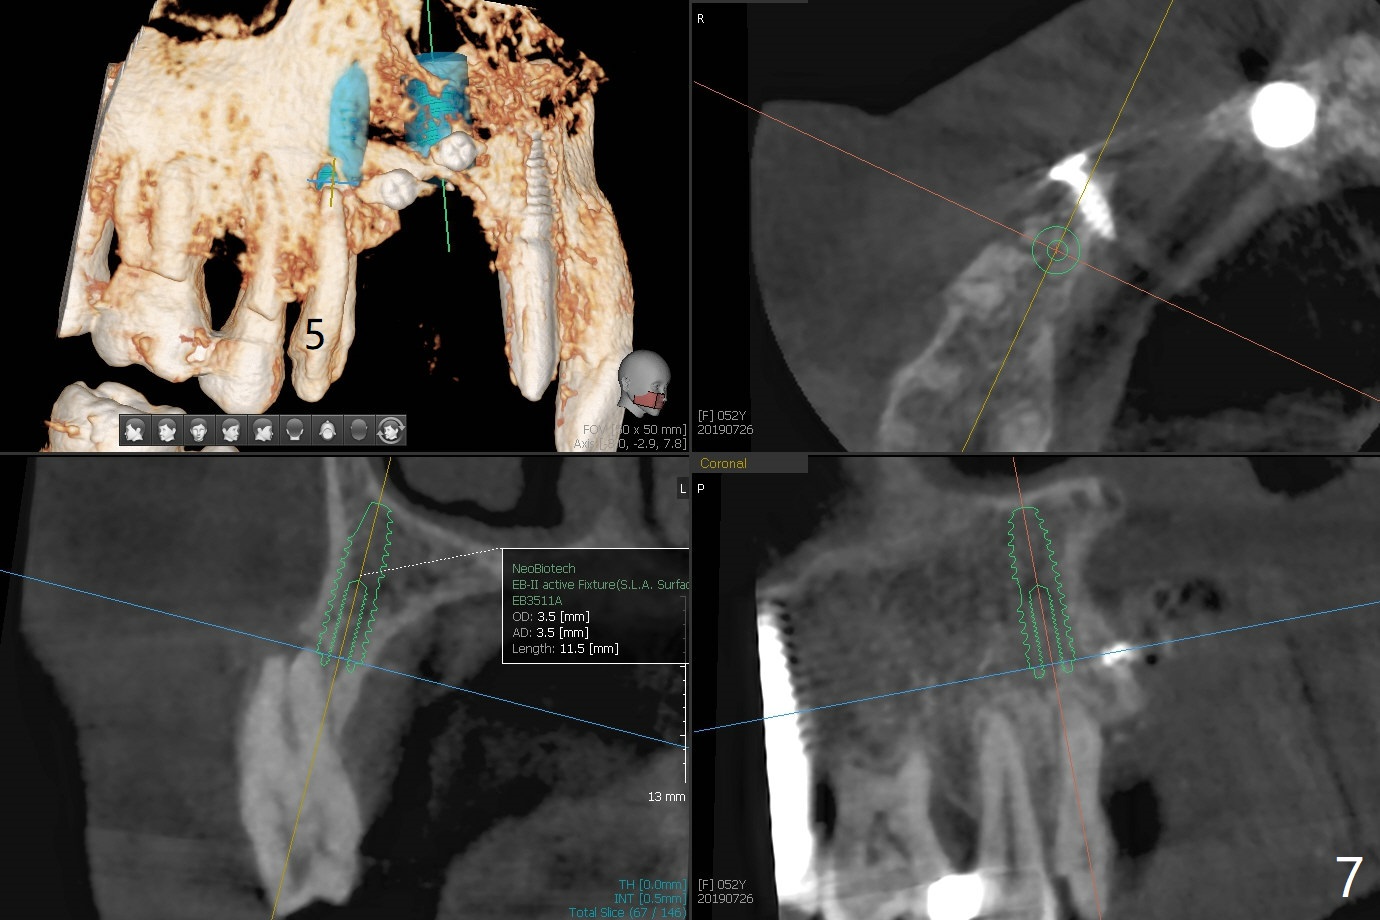

Narrow Implants at #6 and 7

Four months post bone graft with tenting screws at #6 and 7 and implant re-placement at #8, the ridge at #6 and 7 appears to widen slightly, appropriate for narrow implants (Fig.1,2). Guide will be fabricated. The implant at #8 seems to have osteointegrated (Fig.3) with distal gingival recession (Fig.4). One year 5 months later, the tooth #5 is infected with apparently mesial bone loss (Fig.5 *) and papillary erythema and edema (Fig.6). However the pockets are not deep. A gingival embrasure is created between #5 and 6 for self cleansing. The latter does not work. Implants will be placed at #5 and 7 (Fig.7,8).